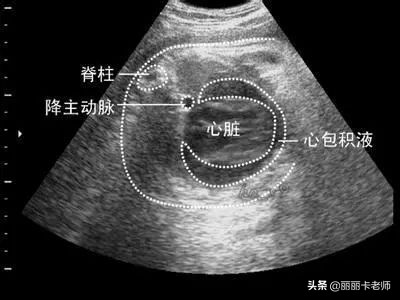

丽丽卡老师:患友,你好!很多肺腺癌的患者在确诊的时候都有心包积液,是因为肺腺癌消耗了人体的蛋白,最后导致血清白蛋白低,然后就出现了心包积液。

一般来说,肺腺癌出现胸水很正常,除非招惹到了心包上,否则这个心包积液不会是癌性积液,应该是蛋白水平低引起的。

如果心包积液特别多,影响了心脏的跳动,出现胸闷、气短这样的症状的时候,需要去医院找医生进行专业的医学治疗或者是直接输白蛋白。

如果心包积液很少,比如说2.5厘米以下,医生一般不会进行专业的治疗。通常心包积液在3厘米以上,医生才会采用医学方式处理。

在输白蛋白或者是口服补蛋白之后,心包积液会一点一点的减少,如果是2.5厘米以下的心包积液,一般在两个月以内就能吸收完。如果再多一点,可能减少的速度会慢一点,但是心包积液不会再出来了。